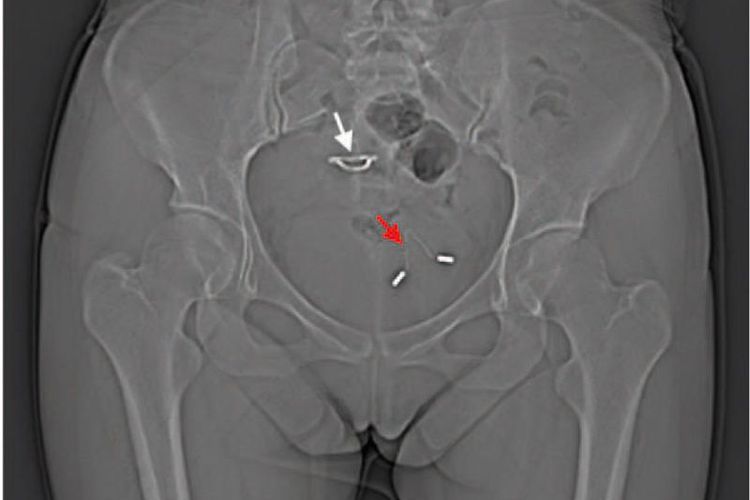

Gara-gara Pakai Alat Kontrasepsi IUD, Wanita Ini Harus Alami Hal Mengerikan

Memilih alat kontrasepsi bagi wanita bisa jadi sangat membingungkan. Pasalnya, tidak ada alat kontrasepsi yang pasti cocok dipakai semua wanita.